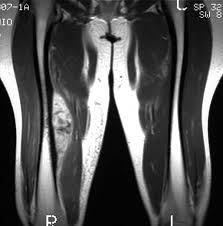

Efecto de una intervención individualizada de auditoría y retroalimentación sobre las tasas de solicitudes de diagnóstico por imágenes musculoesqueléticas por parte de médicos generales australianos

Entre los médicos generales australianos conocidos por solicitar con frecuencia imágenes de diagnóstico musculoesquelético, una auditoría individualizada y una intervención de retroalimentación, en comparación con ninguna intervención, disminuyó significativamente la tasa de pruebas de imágenes musculoesqueléticas dirigidas ordenadas durante 12 meses. JAMA, septiembre de 2022